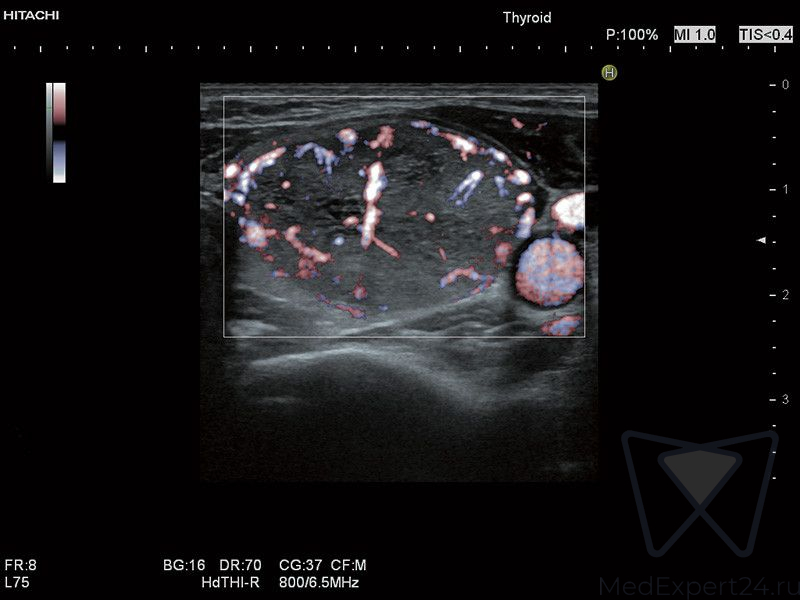

- TDI режим тканевого допплера,